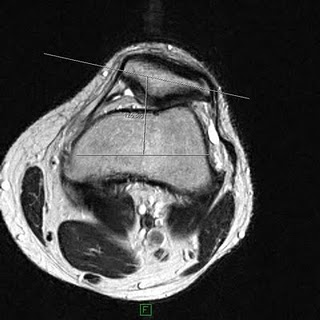

This MRI shows the kneecap of the left knee moving outwards away from the central groove. This can be due to tightness of the lateral knee structures and muscles.